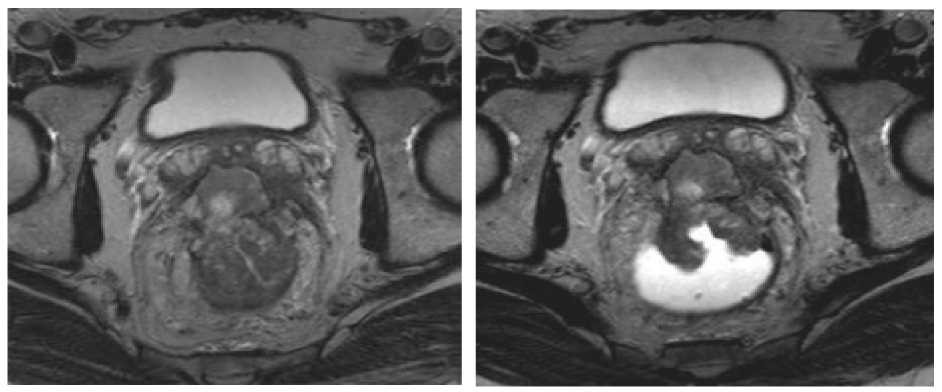

Imágenes de resonancia magnética